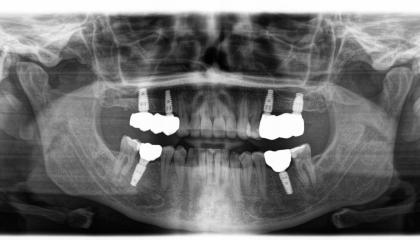

Zirconia bridge on Southern DC Implants